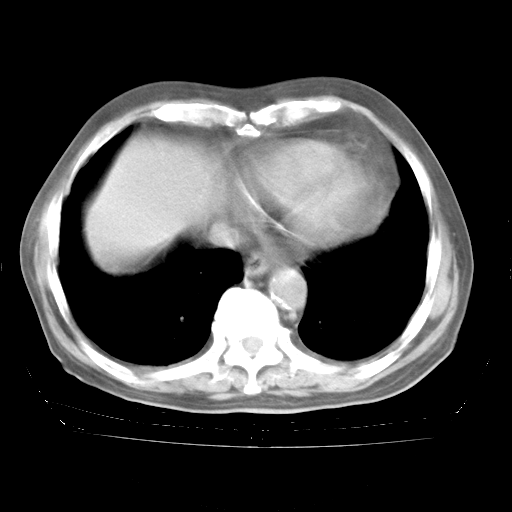

4月28日肺部CT——再次出现类似去年5月9日——透光度降低,“间质性”改变。

4月28日肺部CT——再次出现类似去年5月9日——磨玻璃样、间有“粟粒样”改变。

4月28日肺部CT